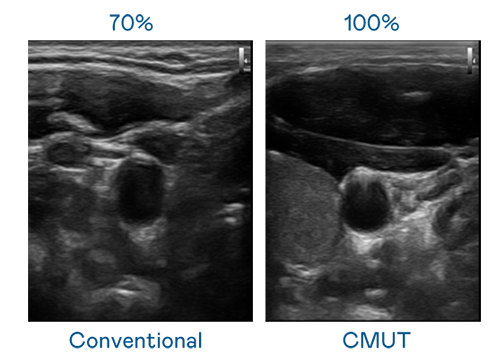

CMUT 技术是一种用电容式微机电元件来产生超音波讯号的技术。与传统 PZT 压电式技术相比,CMUT 频宽增加 30%,更宽频的超音波讯号让影像解析度大幅提升,是实现高影像品质医疗超音波扫描、促进精准医疗发展的关键技术。

超音波影像的解析度高低,首先取决于探头能发出的讯号频宽。DB真人旗舰 CMUT 可提供高清晰的超音波讯号,提供高频宽、高灵敏度、影像纹理细节更高的超音波影像,协助医护人员缩短影像判读时间及利用精准的医疗影像进行诊断。